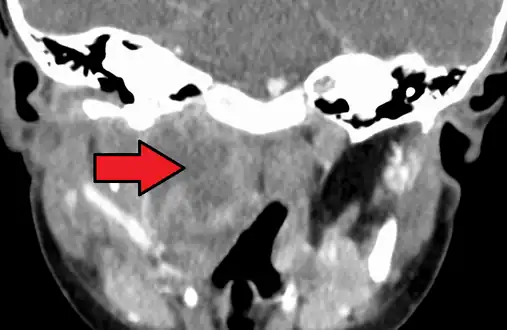

Large retropharyngeal abscess as seen on CT -

Large retropharyngeal abscess as seen on CT

A computed tomography (CT) scan is the definitive diagnostic imaging test.[4]